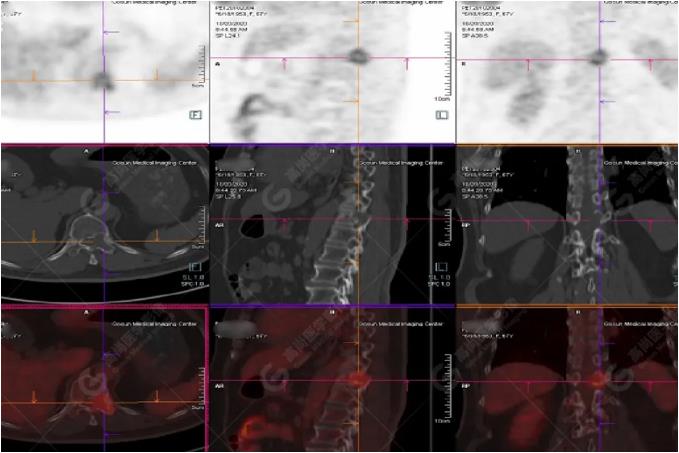

PET/CT影像圖

左胸一后肋溶骨性骨質(zhì)破壞,周?chē)檐浗M織形成,F(xiàn)DG代謝增高,SUVmax為10.9。

找到引起骨痛病灶,病因:原發(fā)?轉(zhuǎn)移?感染?

宮頸一片狀稍低密度影,F(xiàn)DG結(jié)節(jié)樣代謝增高,SUVmax為10.2。